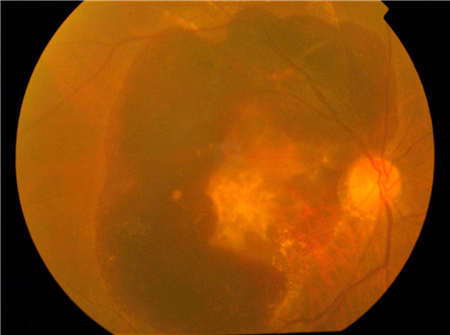

而黃斑變性則發生在視網膜的黃斑部位,即主管中心視力和精細視覺的重要部位。若是黃斑部位發生病變,中心視力自然也會受到影響。雖然干性的黃斑變性一般不對視力造成影響,但如果是濕性黃斑變性又未及時治療,血液和滲出物會積聚在黃斑區,破壞黃斑區的感光細胞,嚴重可導致失明。

而濕性的黃斑變性成因是脈絡膜出現血管增生,這些新生的血管很容易發生滲漏和出血,可導致黃斑區內的感光細胞受損。因此,一旦發現有濕性的黃斑變性,就需要及時進行治療。